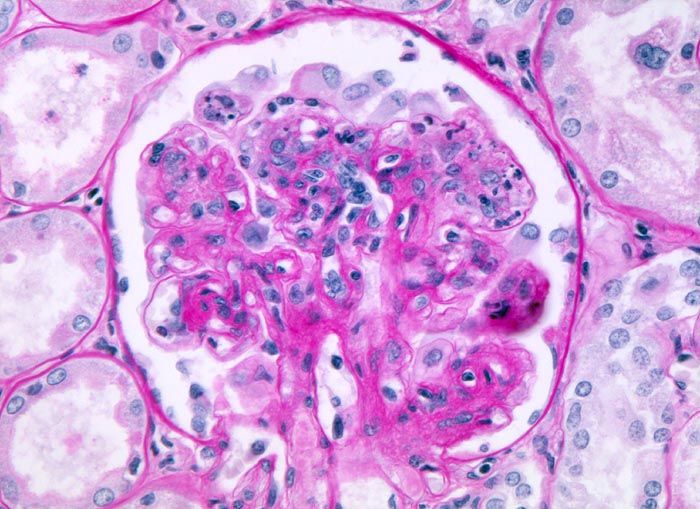

PathoPic – image database / PathoPic ID 4994 - membrano-proliferative Glomerulonephritis Typ I

membrano-proliferative Glomerulonephritis Typ I

Verbreiterung des Mesangiums mit Zellvermehrung. Die Kapillarlumina sind teilweise eingeengt und enthalten Monozyten und neutrophile Granulozyten. Die periphere Basalmembran ist stellenweise verdoppelt. Der Basalmembran sitzen aussen vergrösserte aktivierte Podozyten auf.

Nephrotisches Syndrom, Mikrohämaturie und arterielle Hypertonie. Chronische Hepatitis C.